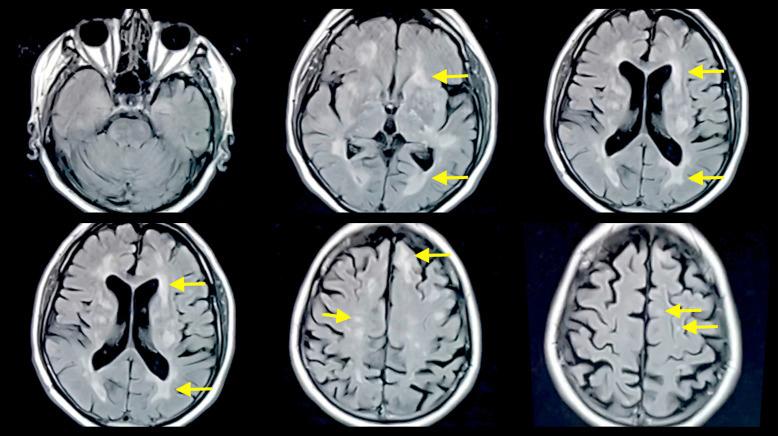

Multiple case reports have shown the presence of multiphasic ADEM without an established cause, emphasizing the importance of additional insight and data in this context. This is a unique case of multiphasic ADEM in a 59-year-old male with a temporal gap of 26 years with an idiopathic cause. He was suffering from many neurologic symptoms involving his upper and lower extremities and level of consciousness, and after he was diagnosed with ADEM, he was commenced on steroids and achieved a marked improvement in his clinical status.

多项病例报告显示存在病因不明的多相性ADEM,强调了在这种情况下深入了解和获取数据的重要性。这是一例59岁男性的独特多相性ADEM病例,两次发病间隔26年,病因不明。他出现了许多涉及上下肢及意识水平的神经症状,在被诊断为ADEM后,开始使用类固醇治疗,临床状况有显著改善。